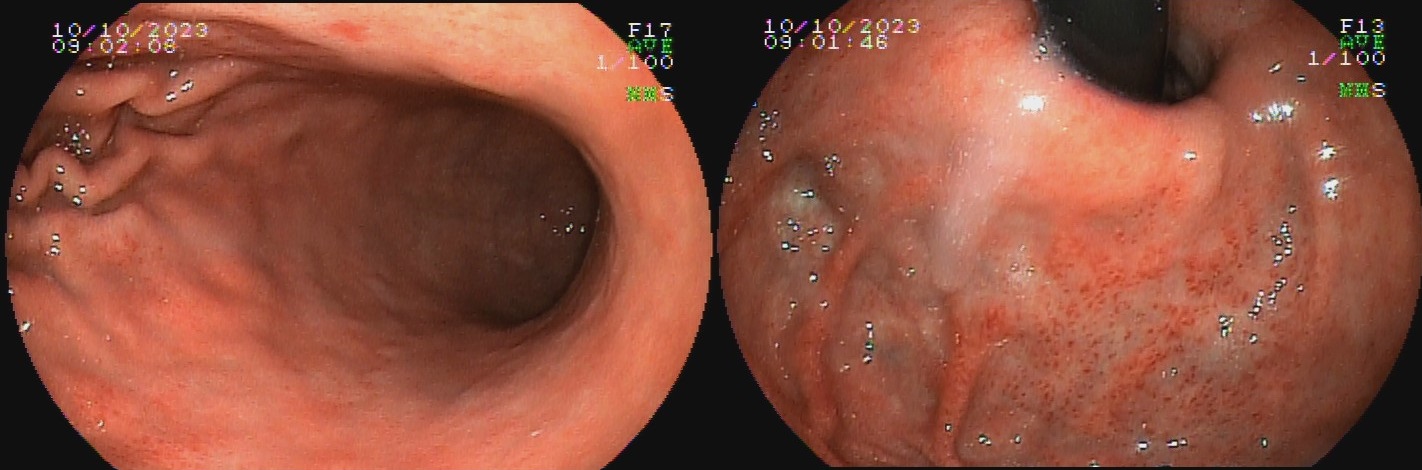

O termo gastrite crônica atrófica refere-se à atrofia da mucosa gástrica causada pelo H. pylori. Inicialmente, a mucosa sofre agressão por neutrófilos, e mais tardiamente, por monócitos. Com o tempo, essa agressão reduz a população de glândulas, tornando o relevo reduzido e a mucosa mais pálida. A diminuição da espessura da camada mucosa torna os vasos da submucosa mais evidentes ao exame endoscópico. Segundo a evolução descrita por Kimura-Takemoto, essa patologia tem início no antro e incisura angular (C1),  e progride em direção à cárdia pela pequena curvatura do corpo, e, após atingir a região mais proximal do estômago (C2 e C3), a progressão inicia abertura da região acometida, expandindo-se em direção às paredes anterior e posterior do corpo e fundo simetricamente (O1 e O2), até acometer a grande curvatura (O3).